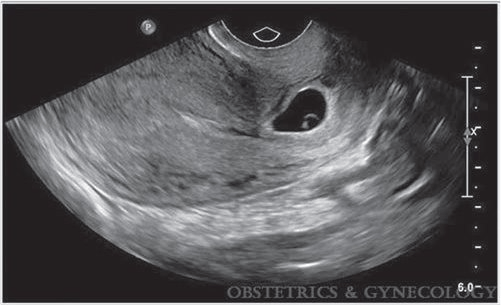

What is a common finding on US that shows "ring of fire sign" but is not an ectopic pregnancy? How can you tell it's not really an ectopic?

corpus luteum

Exert gentle pressure with the transducer or on the anterior abdominal wall to attempt to separate the ectopic pregnancy from the ovary. angle between the ovary and the ectopic pregnancy will be acute because they are adjacent separate structures. Angle will be obtuse between the corpus luteum and the ovary, because the exophytic corpus luteum protrudes from the ovary and exhibits the claw sign.